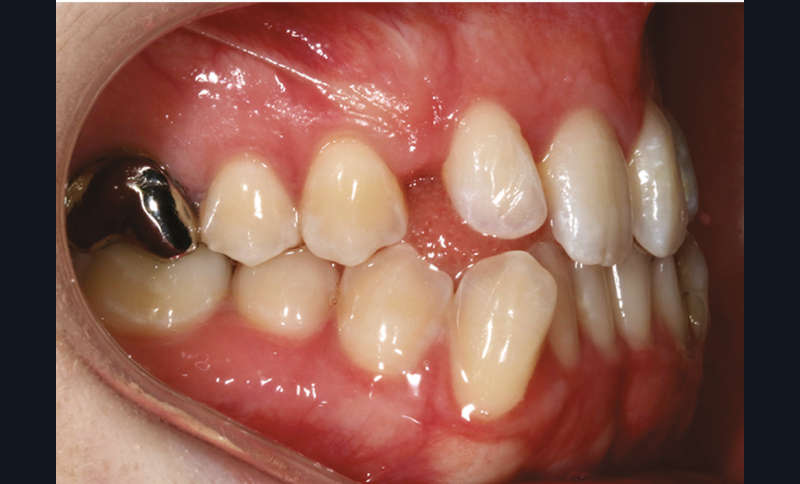

Sur le plan dentaire, on note l’absence des canines maxillaires permanentes sur l’arcade et la persistance de 63. Il existe une DDD par défaut maxillaire (indice de Bolton antérieur 90,2 %) due à l’absence des canines sur l’arcade, mais aussi à une dysharmonie de forme des dents maxillaires (fig. 2a-e).

L’examen radiologique 2D nous confirme l’inclusion de 13 et 23 en position haute, oblique en bas et en avant, couronnes en projection des apex de 11 et 21 et nous permet de quantifier le décalage squelettique (fig. 3 et 4). L‘examen radiologique 3D (cone beam) objective les rapports…